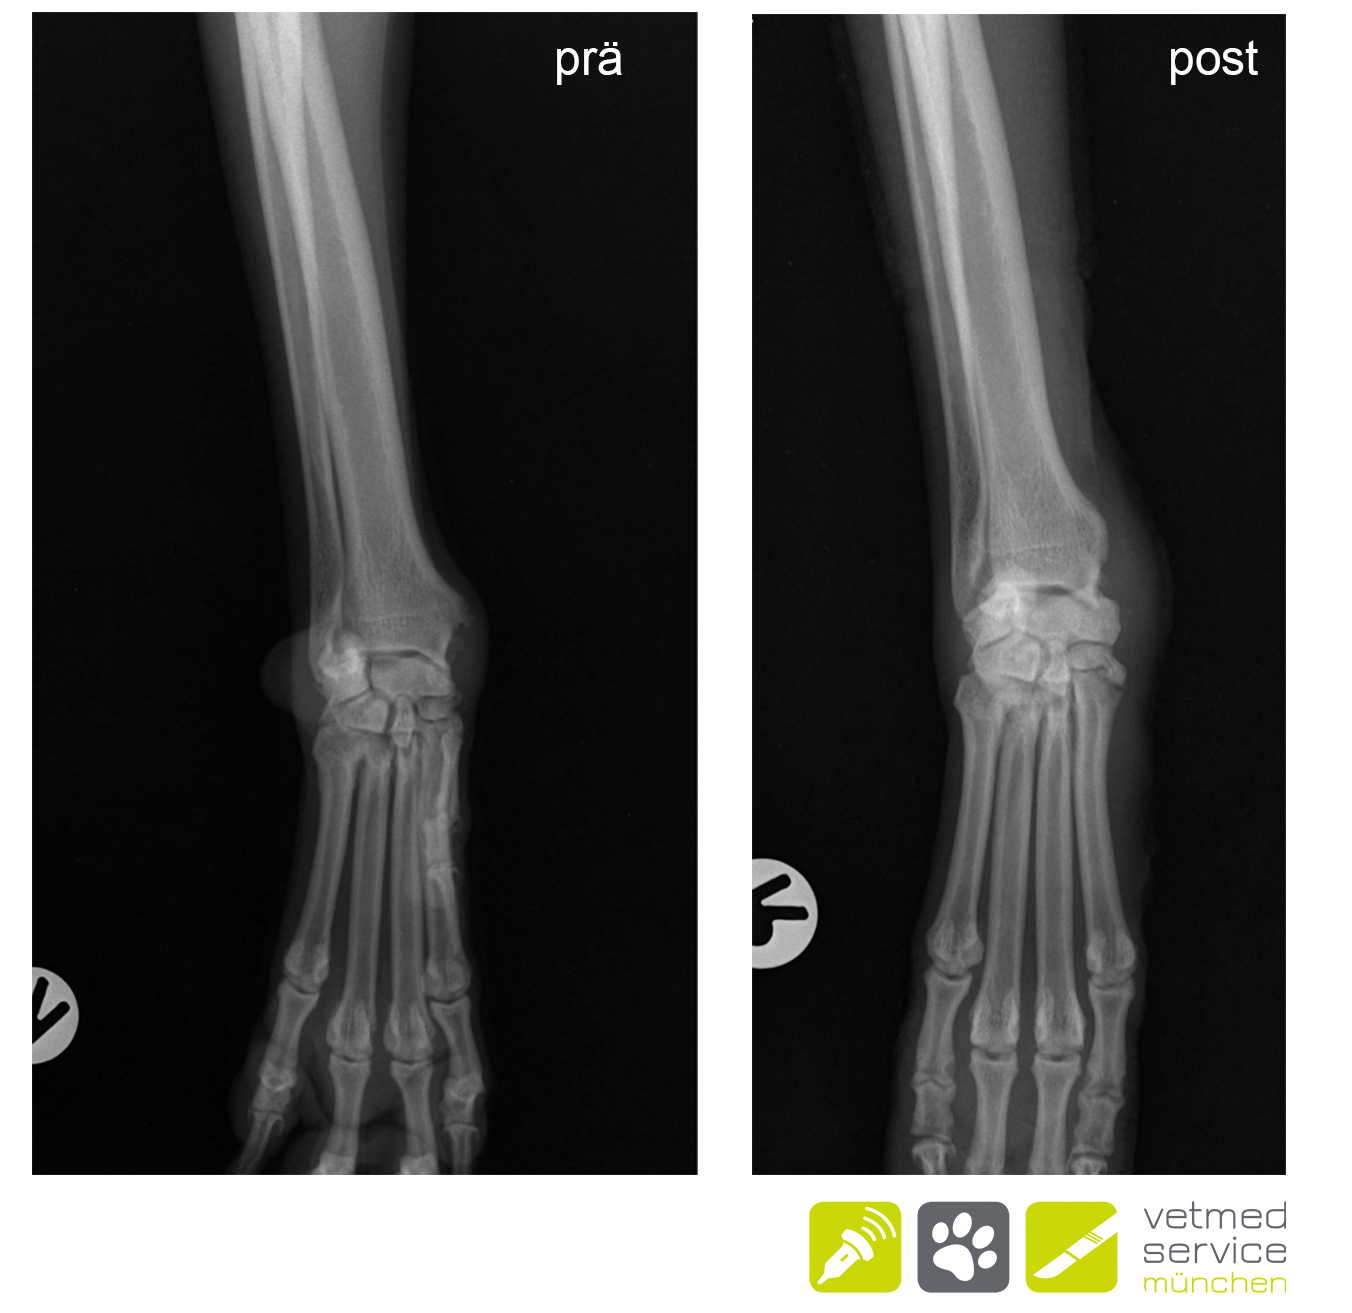

Röntgenologisch zeigten sich Exostosen am medialen Karpus. Das typische Bild einer Tendovaginitis des M. abductor pollicis longus. Da die konservativen Versuche erfolglos blieben, wurde bei „Emma“ eine operative Therapie durchgeführt. Wir haben die Phalanx I amputiert , die Sehne des M. ext. dig. longus freigelegt diese am Übergang zum Muskelbauch abgesetzt, sowie die Exostosen abgetragen. „Emma“ lief bereits kurze Zeit nach der OP lahmheitsfrei und ist es bis heute (7 Monate post OP)

"Meinst du das könnte ein Knochentumor sein und machst du auch Knochenbiopsien?" - Eine berechtigte Frage, beim ersten Blick auf das beigefügte Röntgenbild, denn die röntgenolgischen Veränderungen dieser Erkrankung können an ein Osteosarkom erinnern. Aber es handelt sich um eine Tendovaginitis des M. abductor pollicis longus💡. Obwohl der "Daumen" des Hundes beim Laufen gar nicht wirklich belastet wird, kommt eine chronische Entzündung dieser Sehnenscheide immer wieder vor und führt zu einer chronisch rezidivierenden Lahmheit und zu einer halbkugeligen Schwellung am kraniomedialen Antebrachium. Die röntgenologisch sichtbaren Metaplasien können dem Bild eines Osteosarkoms ähneln. Vergleichende Röntgen der Gegenseite helfen bei der Beurteilung. Falls eine Therapie mit NSAIDs nicht zielführend ist, kann bei schweren Fällen eine Amputation der ersten Zehe und Entfernung der Metaplasien sinnvoll sein.